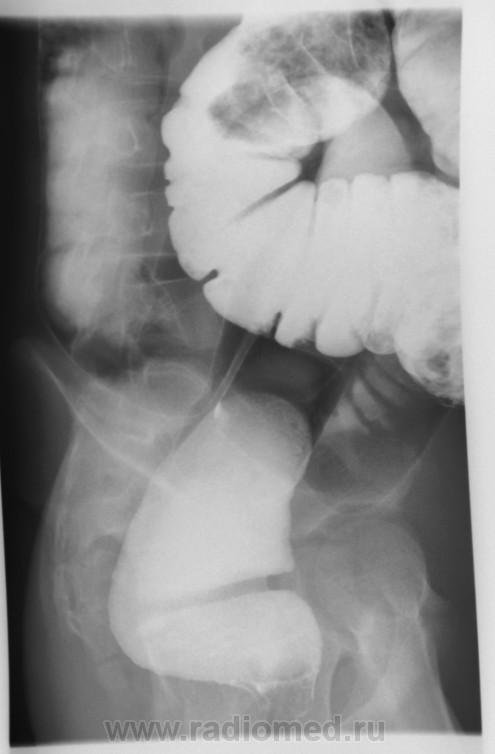

Долихосигма, и плохо очищенная толстая кишка. В детской патологии не силён.

Долихомегасигма, я б сказала, что объясняет клинику запоров. Впрочем, вся кишка расширена. Зоны аганглиоза не видно, на Гиршпрунга не похоже. Селезеночный изгиб не показан адекватно, так что со снимками лежа судить о наличии болезни Пайра проблематично, да и клиники не дано, а жаль.